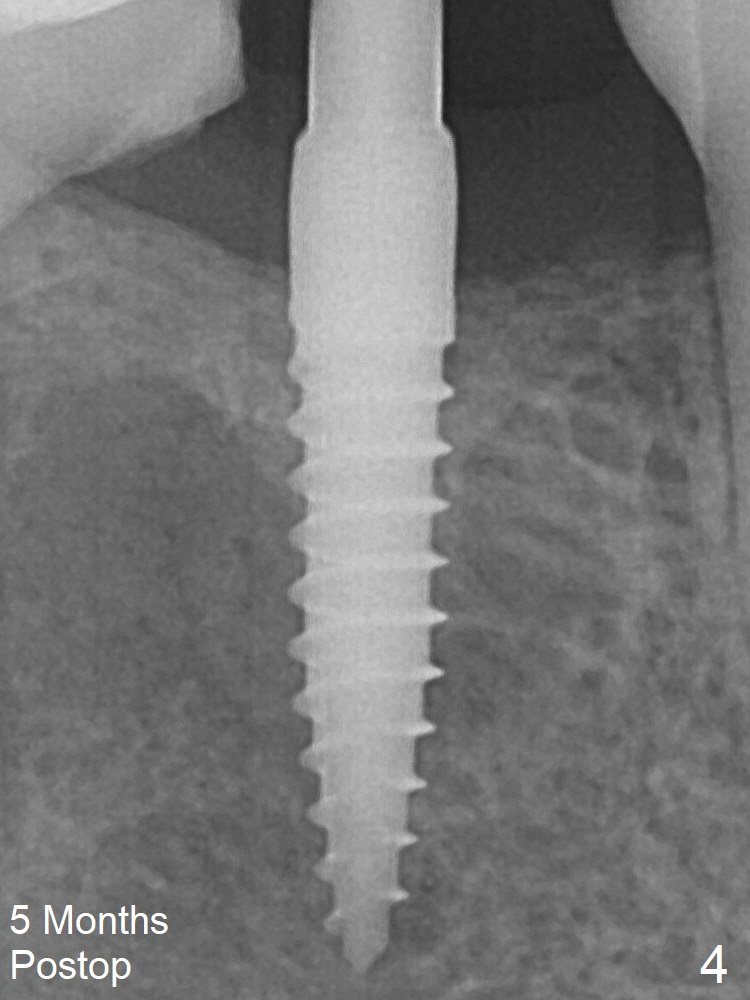

Impression is taken 5 months postop (Fig.4). Residual cement